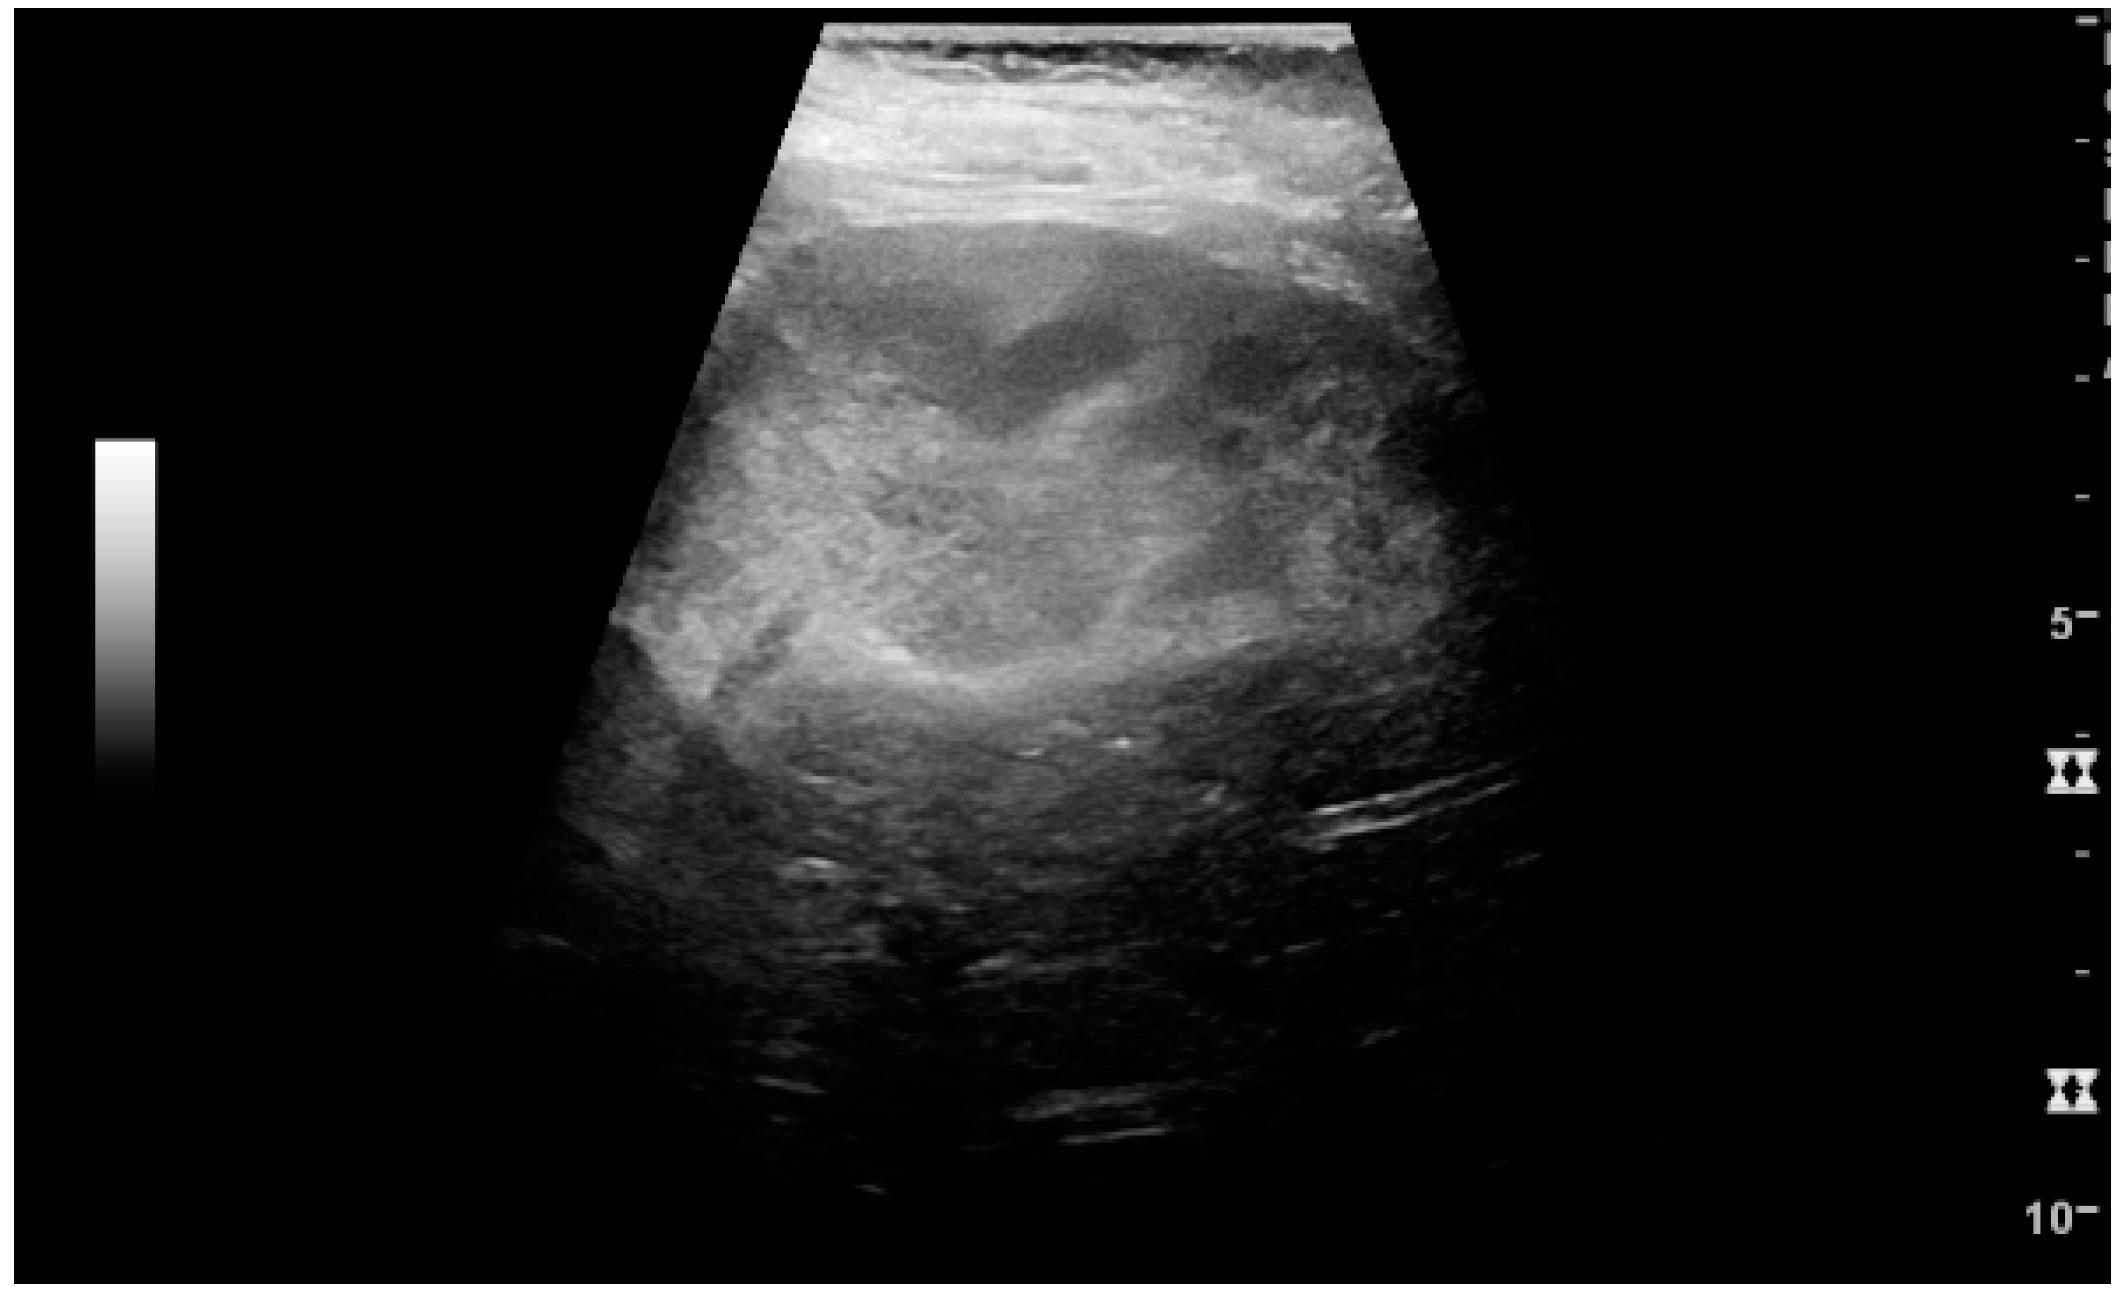

Figure 25. End-stage chronic kidney disease with increased echogenicity, homogenous architecture without visible differentiation between parenchyma and renal sinus and reduced kidney size. Measurement of kidney length on the US image is illustrated by ‘+’ and a dashed line.